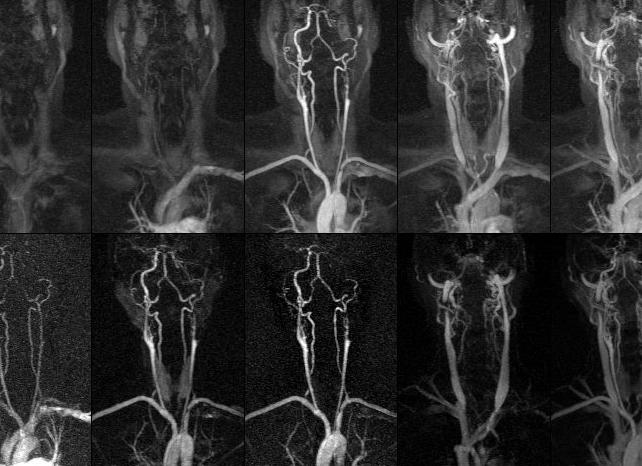

МРТ тонкого и толстого кишечника. Гидро МРТ. Колоноскопия

Существует множество эффективных и достоверных методов выявления патологий желудочно-кишечного тракта. Самыми информативными считаются гидро МРТ, колоноскопия и ирригоскопия, о которых и пойдет речь.